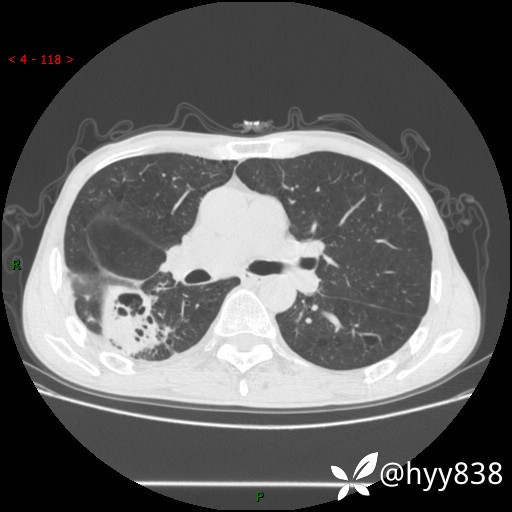

老年男性,肺团片状占位+体重下降,肿瘤 VS 真菌 VS 细菌,看看你的意见--结果公布~

简要病史:患者7天前无明显诱因出现咳嗽咳痰,咳绿色、褐色痰,吸烟后加重,伴心慌、胸闷,无畏寒发热,无头晕头痛,无鼻塞流涕,无痰中带血及咯血,无胸痛、呼吸困难,无全身酸痛,为求进一步诊治于我院就诊,门诊完善胸部CT提示“右下肺团片状影,考虑肿瘤?感染?”,门诊以“咳嗽待查”收住入院。 起病以来,患者精神、饮食、睡眠尚可,大、小便正常,体力下降,体重下降8斤。空腹血糖:6.42mmol/L。

辅助检查:CT

临床诊断:肿瘤?感染?

静脉期